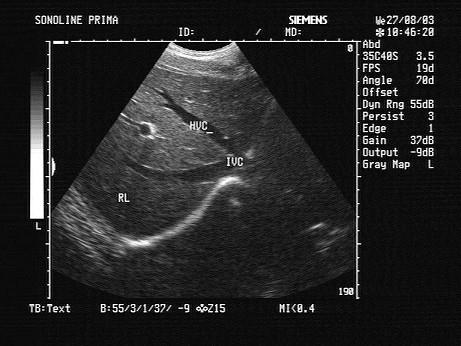

肝脏超声检查中,哪种切面能够显示如图所示声像图?(?)A.肋下斜切B.肋间斜切C.剑下纵切D.肋间横切E.剑下横切

问题 肝脏超声检查中,哪种切面能够显示如图所示声像图?(?)

选项 A.肋下斜切 B.肋间斜切 C.剑下纵切 D.肋间横切 E.剑下横切

答案 A